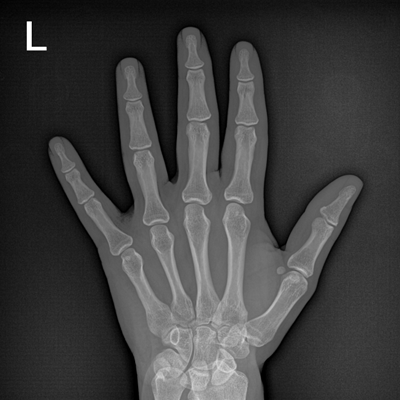

輕量化設(shè)計(jì) 小巧靈活 PLX5100

用于影像科、急診室、病房、ICU、手術(shù)室等多場景應(yīng)用。

● 數(shù)字化無線平板成像,操作簡便,成像質(zhì)量高